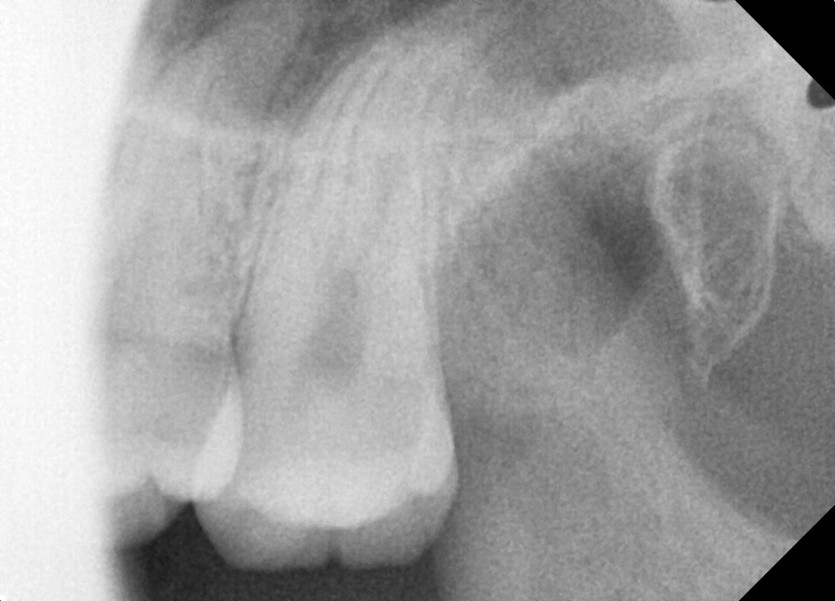

#28,38 사랑니 발치

구강 외과 전문의가 당일 발치했습니다.